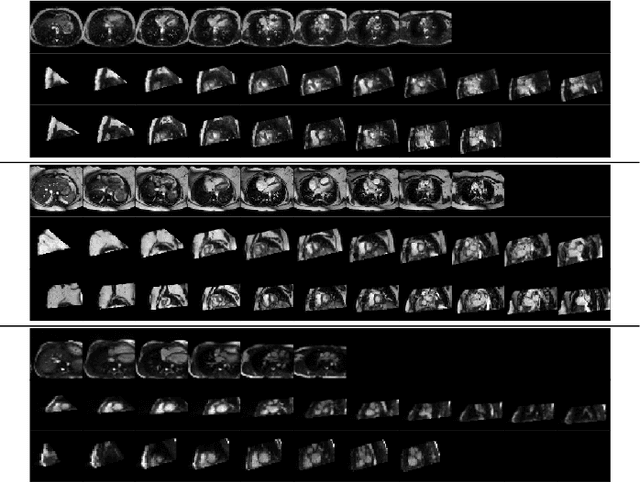

Abstract:Cardiac magnetic resonance (CMR) sequences visualise the cardiac function voxel-wise over time. Simultaneously, deep learning-based deformable image registration is able to estimate discrete vector fields which warp one time step of a CMR sequence to the following in a self-supervised manner. However, despite the rich source of information included in these 3D+t vector fields, a standardised interpretation is challenging and the clinical applications remain limited so far. In this work, we show how to efficiently use a deformable vector field to describe the underlying dynamic process of a cardiac cycle in form of a derived 1D motion descriptor. Additionally, based on the expected cardiovascular physiological properties of a contracting or relaxing ventricle, we define a set of rules that enables the identification of five cardiovascular phases including the end-systole (ES) and end-diastole (ED) without the usage of labels. We evaluate the plausibility of the motion descriptor on two challenging multi-disease, -center, -scanner short-axis CMR datasets. First, by reporting quantitative measures such as the periodic frame difference for the extracted phases. Second, by comparing qualitatively the general pattern when we temporally resample and align the motion descriptors of all instances across both datasets. The average periodic frame difference for the ED, ES key phases of our approach is $0.80\pm{0.85}$, $0.69\pm{0.79}$ which is slightly better than the inter-observer variability ($1.07\pm{0.86}$, $0.91\pm{1.6}$) and the supervised baseline method ($1.18\pm{1.91}$, $1.21\pm{1.78}$). Code and labels will be made available on our GitHub repository. https://github.com/Cardio-AI/cmr-phase-detection

Abstract:Anisotropic multi-slice Cardiac Magnetic Resonance (CMR) Images are conventionally acquired in patient-specific short-axis (SAX) orientation. In specific cardiovascular diseases that affect right ventricular (RV) morphology, acquisitions in standard axial (AX) orientation are preferred by some investigators, due to potential superiority in RV volume measurement for treatment planning. Unfortunately, due to the rare occurrence of these diseases, data in this domain is scarce. Recent research in deep learning-based methods mainly focused on SAX CMR images and they had proven to be very successful. In this work, we show that there is a considerable domain shift between AX and SAX images, and therefore, direct application of existing models yield sub-optimal results on AX samples. We propose a novel unsupervised domain adaptation approach, which uses task-related probabilities in an attention mechanism. Beyond that, cycle consistency is imposed on the learned patient-individual 3D rigid transformation to improve stability when automatically re-sampling the AX images to SAX orientations. The network was trained on 122 registered 3D AX-SAX CMR volume pairs from a multi-centric patient cohort. A mean 3D Dice of $0.86\pm{0.06}$ for the left ventricle, $0.65\pm{0.08}$ for the myocardium, and $0.77\pm{0.10}$ for the right ventricle could be achieved. This is an improvement of $25\%$ in Dice for RV in comparison to direct application on axial slices. To conclude, our pre-trained task module has neither seen CMR images nor labels from the target domain, but is able to segment them after the domain gap is reduced. Code: https://github.com/Cardio-AI/3d-mri-domain-adaptation

Abstract:Planning the optimal time of intervention for pulmonary valve replacement surgery in patients with the congenital heart disease Tetralogy of Fallot (TOF) is mainly based on ventricular volume and function according to current guidelines. Both of these two biomarkers are most reliably assessed by segmentation of 3D cardiac magnetic resonance (CMR) images. In several grand challenges in the last years, U-Net architectures have shown impressive results on the provided data. However, in clinical practice, data sets are more diverse considering individual pathologies and image properties derived from different scanner properties. Additionally, specific training data for complex rare diseases like TOF is scarce. For this work, 1) we assessed the accuracy gap when using a publicly available labelled data set (the Automatic Cardiac Diagnosis Challenge (ACDC) data set) for training and subsequent applying it to CMR data of TOF patients and vice versa and 2) whether we can achieve similar results when applying the model to a more heterogeneous data base. Multiple deep learning models were trained with four-fold cross validation. Afterwards they were evaluated on the respective unseen CMR images from the other collection. Our results confirm that current deep learning models can achieve excellent results (left ventricle dice of $0.951\pm{0.003}$/$0.941\pm{0.007}$ train/validation) within a single data collection. But once they are applied to other pathologies, it becomes apparent how much they overfit to the training pathologies (dice score drops between $0.072\pm{0.001}$ for the left and $0.165\pm{0.001}$ for the right ventricle).